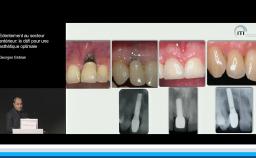

Cette présentation s’intéresse à l’influence des étapes chirurgicales sur le résultat esthétique en implantologie.

Il est communément admis qu’une épaisseur minimale de gencive kératinisée autour des implants est favorable au résultat esthétique mais aussi au maintien d’une bonne santé des tissus péri-implantaires au long terme, mais il n’existe pas de consensus à ce niveau. Une épaisseur osseuse de 2 mm autour des implants est nécessaire pour prévenir les résorptions osseuses et pour soutenir de façon pérenne les tissus mous.

Le moment de l’implantation (immédiate, précoce, différée) influe peu sur le résultat esthétique ; l’implantation immédiate ne supprime pas la résorption physiologique post-extractionnelle.

Tous les types d’implants peuvent être utilisés en secteur antérieur, mais l’utilisation de connexions au niveau osseux offre plus de latitude sur le placement de l’implant et sur la réhabilitation prothétique. Afin de limiter les proximités entre implants et entre dents et implants, l’utilisation d’implants de faible diamètre et la réduction du nombre d’implants sont des options à considérer.